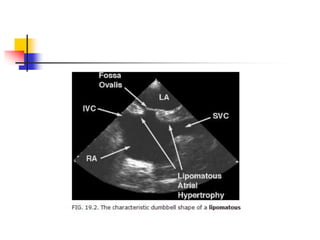

 lipomatous hypertrophy refers the condition of

prominent thickening of interatrial septum, usually > 2

cm, caused by excessive fatty infiltration.

 it actually represents the fat-filled extracardiac

spaces which is not encapsulated unlike true lipoma.

 Echocardiographic diagnosis is made when a marked

atrial septal thickening > 15-20 mm in the absence of

any other explanation for the abnormal thickening.

 region of fossa ovalis is typically spared, which

makes a characteristic dumbbell- or hour glass-

shaped lesion.

 Subcostal window can be best used . ME bicaval

view differentiates lipomatous hypertrophy from other

structures.

 superior and inferior "mass" is corresponds to the fat-

filled groove between atria (Waterston's groove) and

ventricles (inferior pyramidal space), respectively.

Lipomatous Hypertrophy of theAtrial Septum  lipomatous hypertrophy refers the condition of prominent thickening of interatrial septum, usually > 2 cm, caused by excessive fatty infiltration.  it actually represents the fat-filled extracardiac spaces which is not encapsulated unlike true lipoma.  Echocardiographic diagnosis is made when a marked atrial septal thickening > 15-20 mm in the absence of any other explanation for the abnormal thickening.

• 30.

 region offossa ovalis is typically spared, which makes a characteristic dumbbell- or hour glass- shaped lesion.  Subcostal window can be best used . ME bicaval view differentiates lipomatous hypertrophy from other structures.  superior and inferior "mass" is corresponds to the fat- filled groove between atria (Waterston's groove) and ventricles (inferior pyramidal space), respectively.